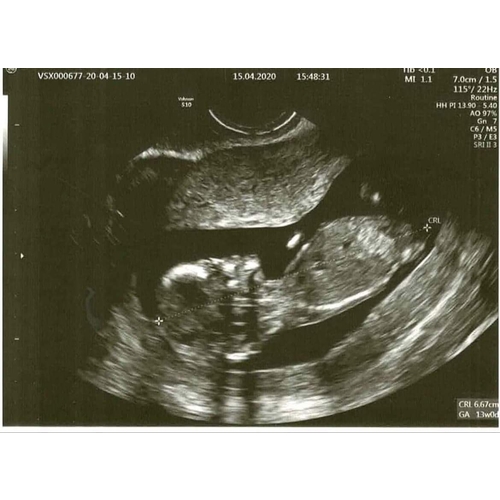

Eigenlijk niets.. het viel me gewoon op dat er bij mij geen neusje te zien is, tov andere echo's. Intussen wat aan andere mensen laten zien en ze denken dat de foetus gedraaid is, en daarom het neusje niet zichtbaar is. En t neusje is niet gelijk aan t neusbotje, dat wist ik niet (ookal is dat superlogisch eigenlijk..).